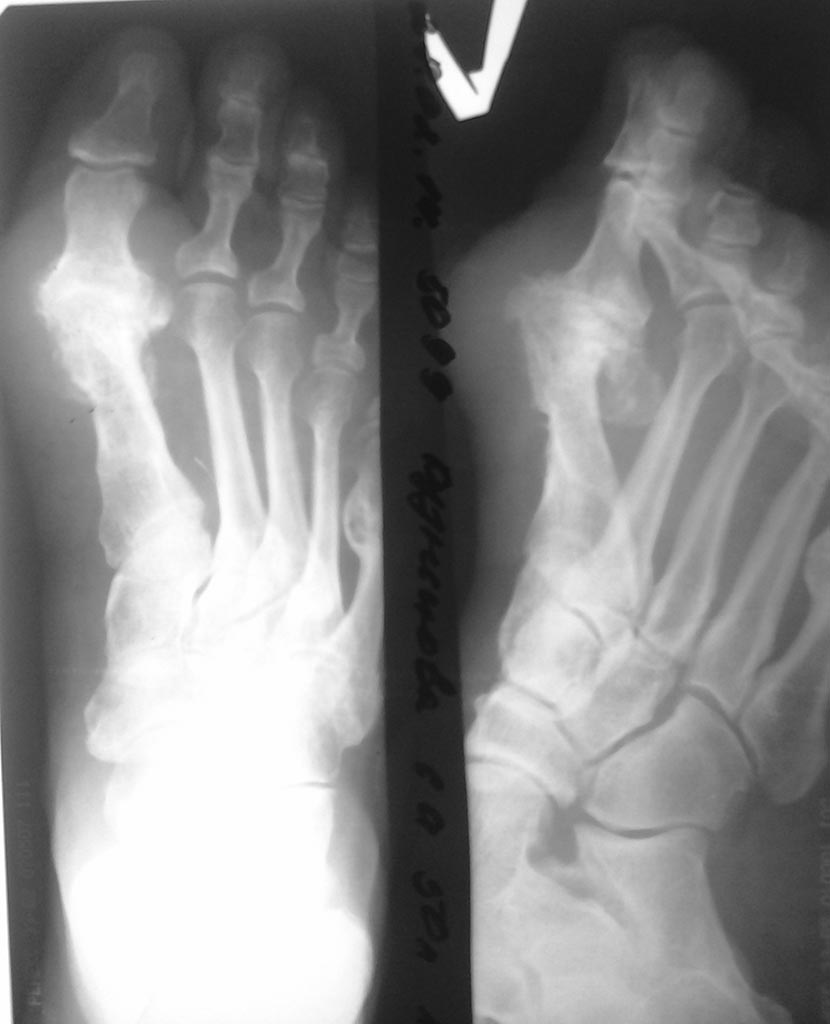

Доброе время суток, помогите пожалуйста с тактикой лечения. Пациентке 50

лет в анамнезе корректирующая операция на костях 1 луча левой стопы, в

настоящее время беспокоят боли в проекции 1 луча при опоре на

стопу.Рентгенологически и клинически артродез 1 плюсне-фалангового

сустава состоялся. Что-бы Вы порекомендовали в плане лечения.